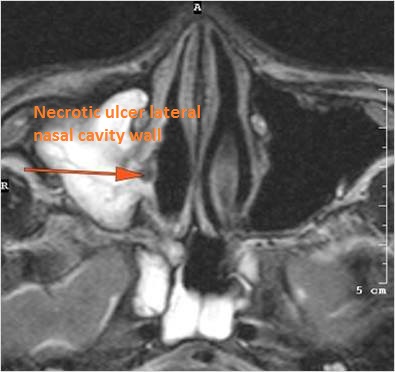

There is focal area of mucoperiosteal thickening or a destructive, ulcerative or necrotic abnormality of the nasal septum turbinates or lateral walls of the nasal cavity. [Yes/No]